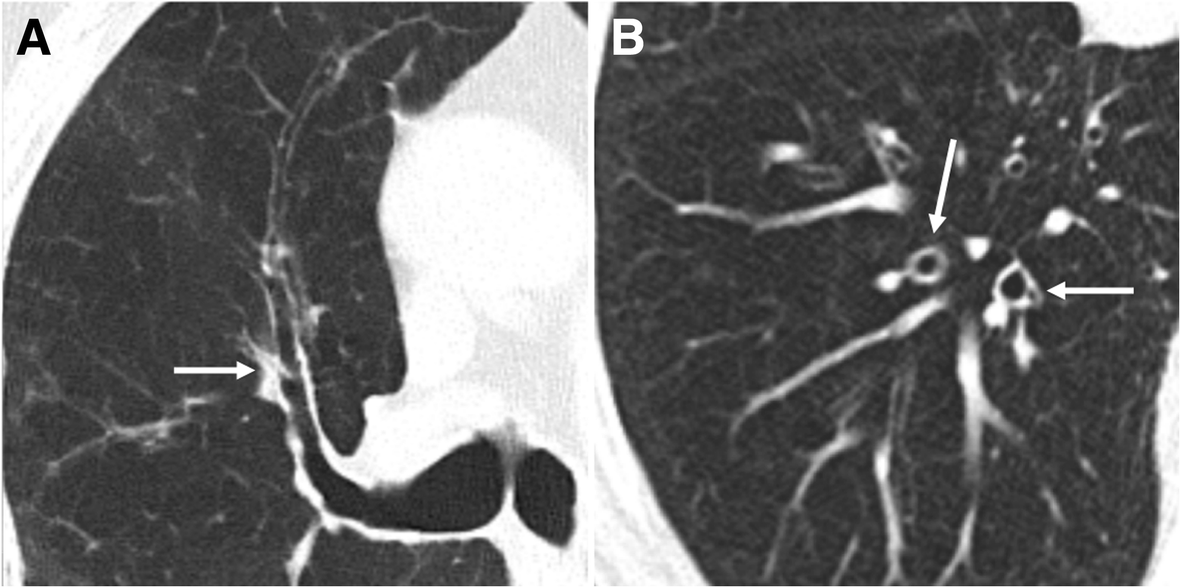

Diffuse smokingrelated lung diseases insights from a radiologic Smoking Related Lung Disease Radiographics can ct imaging be used to identify clinical phenotypes of smoking related lung disease that have specific bronchial. from the pathologist's perspective, the most characteristic effect of tobacco smoke on lung parenchyma is rb, consisting of the presence of. consensus between the clinical, radiographic, and pathologic findings is important in identifying and differentiating between the. there. Smoking Related Lung Disease Radiographics.